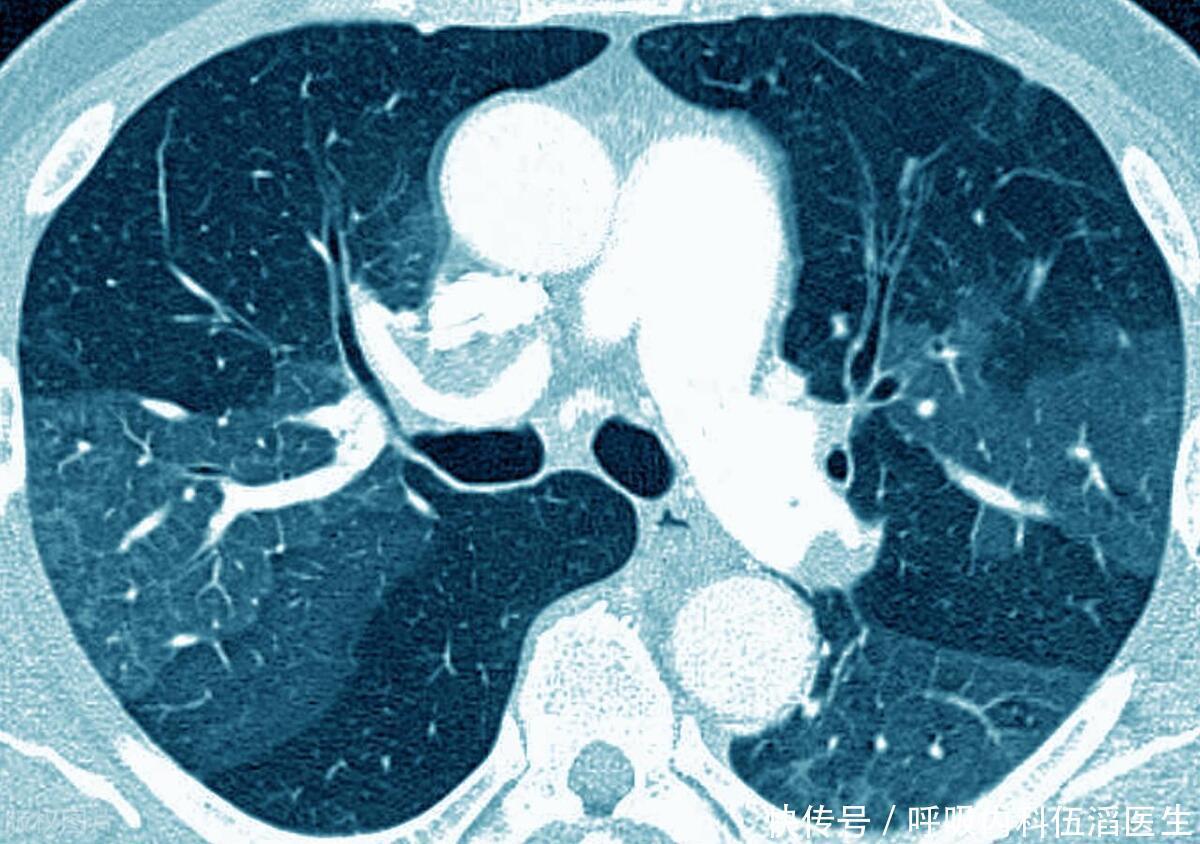

肺开始“癌变”时,身体或会出现 5 种症状,医生提醒:最好别大意